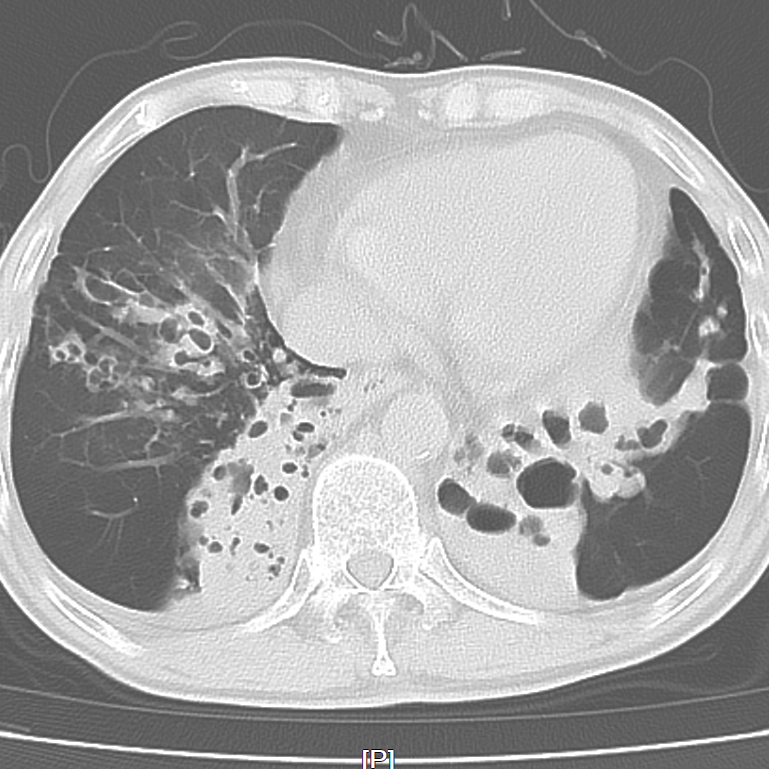

图片

▲患者肺部CT

近日,外一科就收治了这样一位呼吸科的老病号,两个月前,老姚(化名)刚于呼吸科出院,出院诊断:支气管扩张伴感染、慢性支气管炎、肺气肿,痰培养为铜绿假单胞杆菌。

此次因胆囊结石伴胆囊炎、胆总管结石收治入院,其实患者的胆结石也是他的“老难题”了,前些年就想积极手术,奈何肺功能太差,辗转几次无果。除了手术本身的风险以外,围手术期心肺意外的风险很大,很有可能手术后气管插管拔管困难,需进ICU呼吸机支持。术后也同样存在肺不张、肺部感染、心衰等并发症。